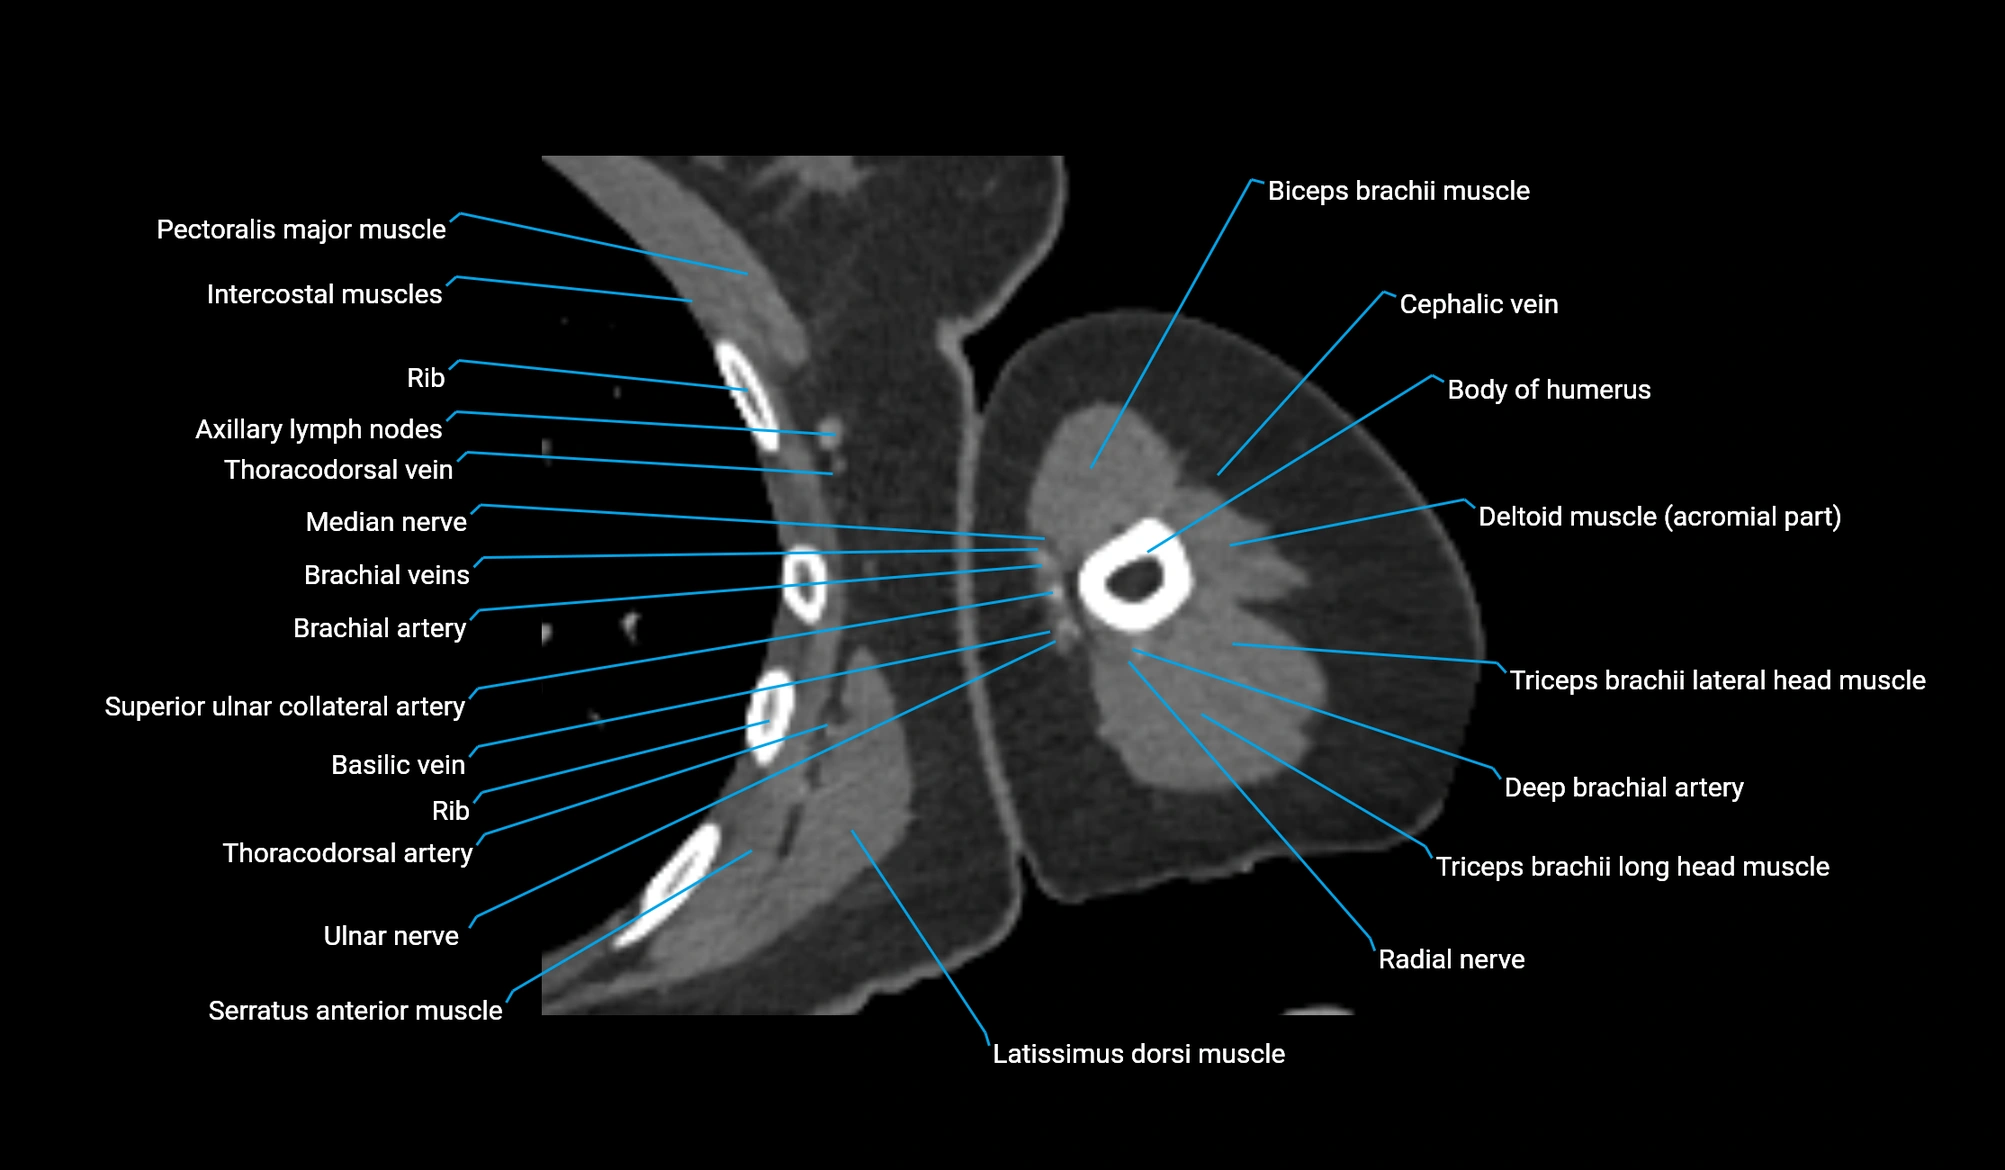

CT image